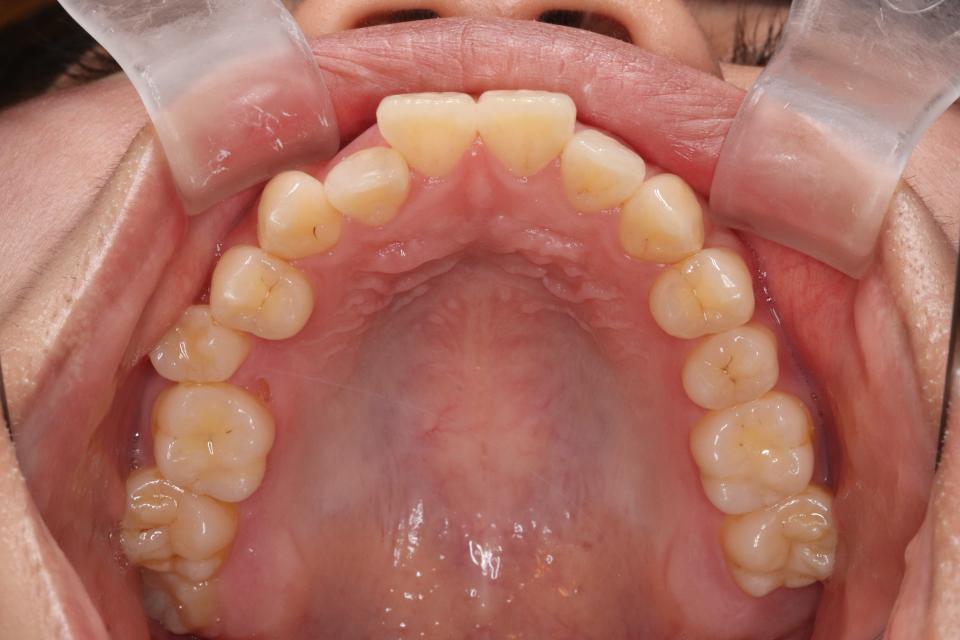

矯正治療前

前歯が出ているのと隙間が気になる、と当院に来院されました。

目立たない装置・取り外し可能なマウスピースタイプでの矯正治療を

希望されてましたので親知らずを4本抜歯して、歯のやすりがけ(IPR)をし、マウスピース型矯正装置(インビザライン)で矯正治療を行いました。